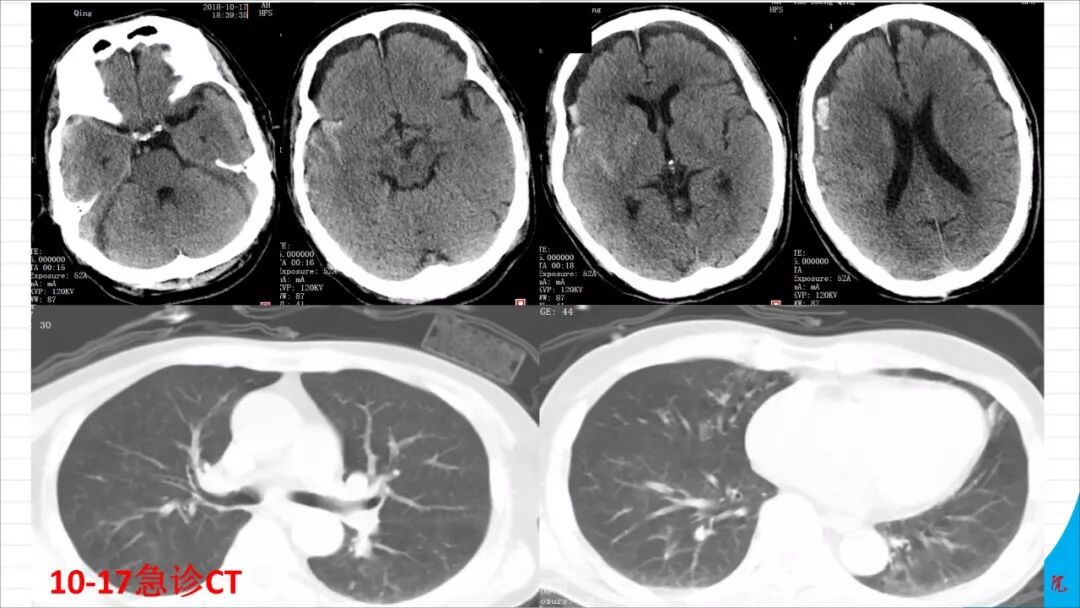

今天为大家分享的是《颅脑创伤-神经重症病例周刊》第113期,由株洲市三三一医院神经外科毛德龙医师带来的:老年病人慢性硬膜下血肿自然演变一例 ,天津医科大学总医院神经外科副主任兼NICU主任、“神外资讯中国颅脑创伤-神经重症专家组”委员江荣才教授对病例作出了精彩点评,欢迎观看、阅读。